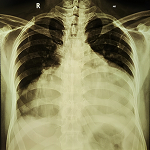

What about covid-19 and oxidative stress? SARS-CoV2, probably like other RNA viruses [4] can trigger an oxidative stress. This hypothesis can easily be checked by the dosage of oxidative stress markers [7] in the blood of sick people of COVID-19. A cytokin storm with hyper inflammation had been found in these patients [9] but researchers should also chek for a possible oxidative storm with all he deleterious effects of RONS, notably lipid peroxydation and proteins oxidation of membranes which can contribute to the transformation, hyalinization of pulmonary alveolar membranes [11] with letal respiratory distress. As elders and people suffering of diabetes, hypertension and cardiovascular diseases have already a state of oxidative stress [2,3], viral infection will increasae this stress, giving us one possible explanation of the severity of COVID-19 in these categories of patients [12].